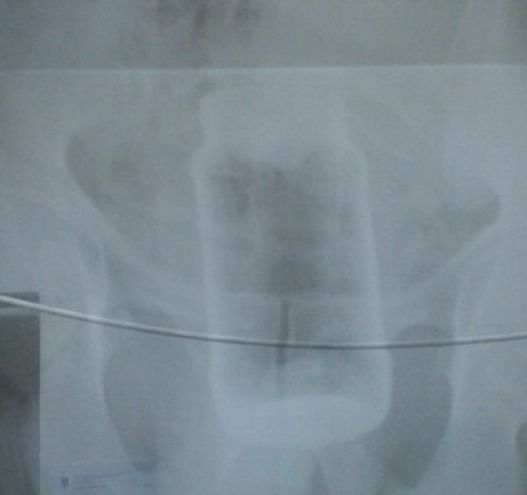

Totul a început miercuri, în jurul orei 11.00, cu un apel la 112. Cel care a sunat a cerut ajutorul Ambulanţei, deoarece avea o durere puternică în zona burţii. „Ajuns la adresa indicată, personalul medical a fost uimit să constate că durerile abdominale erau cauzate de un borcan de dimensiuni apreciabile (400 de ml, n.r.), introdus în anus. Bărbatul a fost transportat în condiţii de siguranţă la Spitalul Judeţean, pentru îngrijiri medicale de specialitate”, declară dr. Mihai Polinschi, directorul Serviciului de Ambulanţă Galaţi.

Medicul-şef al UPU – SMURD Galaţi, dr. Angel Trifan, a explicat de ce a fost nevoie de operaţie. „Poziţia obiectului străin era prea avansată, motiv pentru care s-a luat decizia medicală de extragere printr-o intervenţie chirurgicală. Ca orice operaţie pe abdomen, şi aceasta a fost una dificilă. Oricum, în momentul de faţă starea pacientului este una bună, el rămânând totuşi internat pentru recuperare. În astfel de cazuri se poate ajunge inclusiv până la deces, mai ales dacă obiectul este unul casant şi, prin spargere, riscă să perforeze intestinul şi organele din imediata vecinătate a acestuia”, explică dr. Trifan.